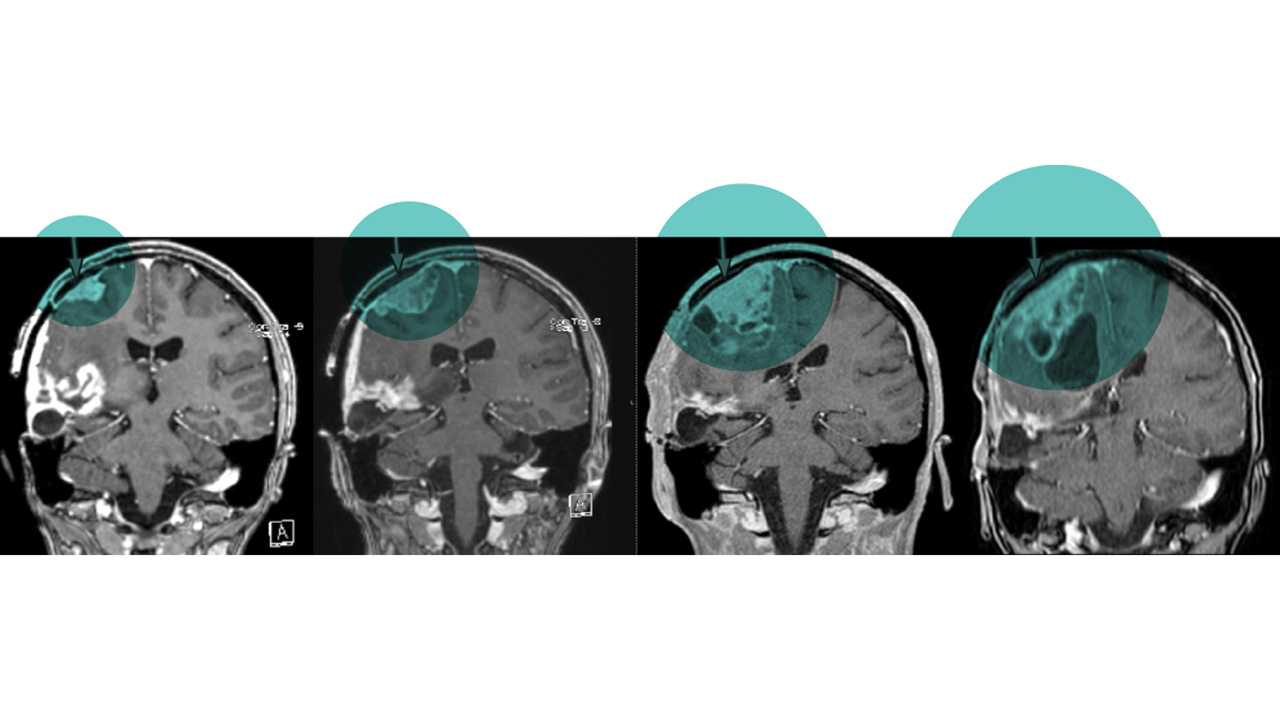

One such diagnosis is diffuse intrinsic pontine glioma, or DIPG. This high-grade glioma, typically nestled within a region of the brainstem known as the pons, is 100% fatal within five years; most patients don’t live longer than 11 months after diagnosis. Currently, the only treatment physicians pursue for DIPG is radiation, and even that is just a palliative measure.

Dr. Venkataraman’s work extends beyond improving current radiation treatments to finding entirely new solutions, as well. One of the major challenges to treating DIPG tumors is their location in the pons. In order to reach the tumor, a drug must be able to cross the blood-brain barrier — a selective semipermeable wall of cells that keeps harmful substances from affecting the brain. This barrier has rendered chemotherapy useless against DIPG.